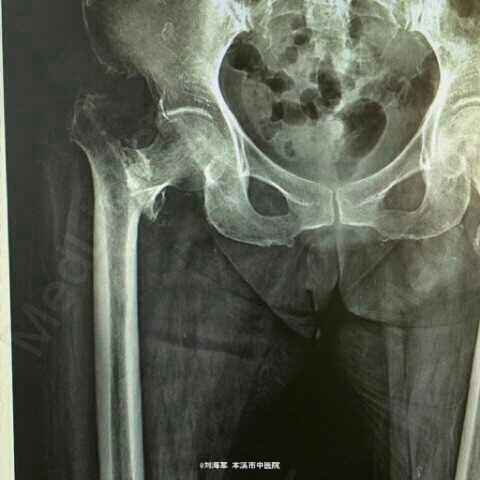

患者女性,65岁,以摔伤后右髋刺痛,活动受限2小时来诊。诉约2小时前走路不慎摔倒,右髋着地,出现右髋刺痛,活动受限。为求症状缓解而来我院。经门诊拍片以“右股骨颈骨折”入院。伤后无头痛,头晕,无恶心呕吐,伤前饮食二便正常。

查体:右髋屈曲外旋短缩畸形,活动受限,右腹股沟中点压痛阳性,右髋叩痛阳性,右大腿纵向叩击痛阳性。 拍片示:右股骨颈骨折

诊断:右股骨颈基底部骨折 治疗:行人工股骨头置换术